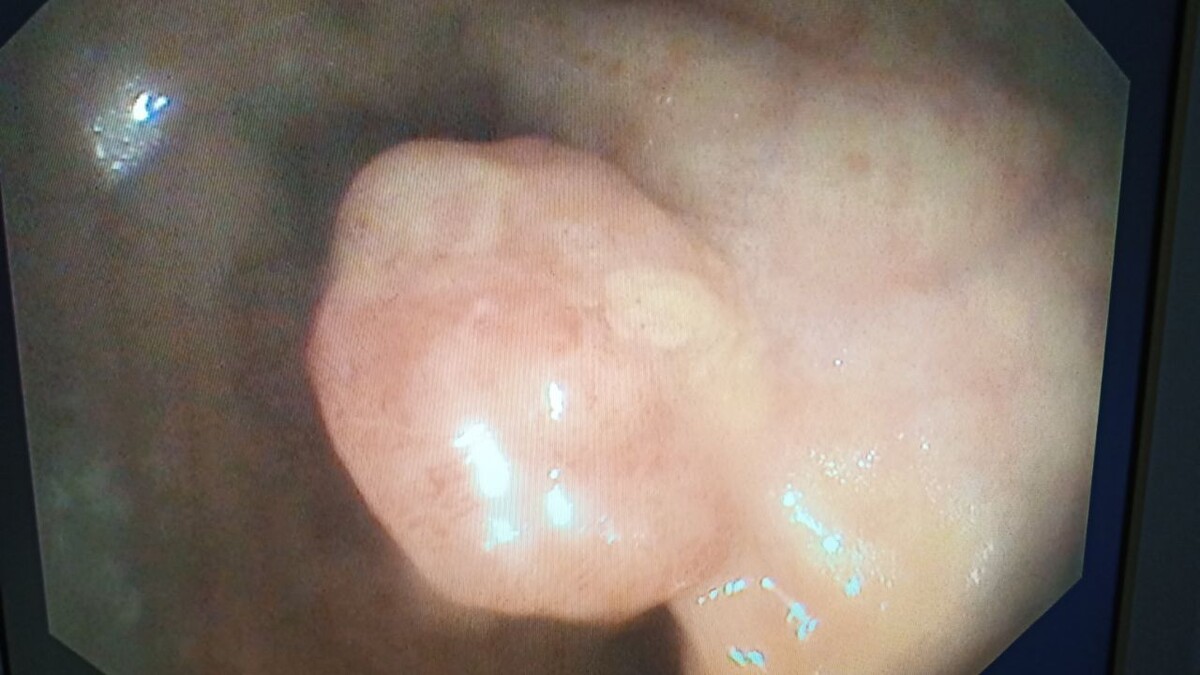

Сегодняшняя находка при плановой колоноскопии. Пациентка 60 лет. Жалоб не было. Полип в средней трети прямой кишки 1,5 см в диаметре. По внешнему виду - тубулярная аденома. Ждём гистологию. Записал на плановое удаление.